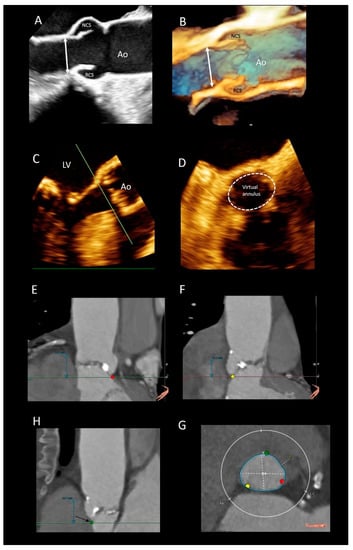

3.5. The Aortic Annulus

3.6. The Interleaflets Triangles

3.7. The Sinuses of Valsalva

3.8. Leaflets

3.9. The Sinutubular Junction